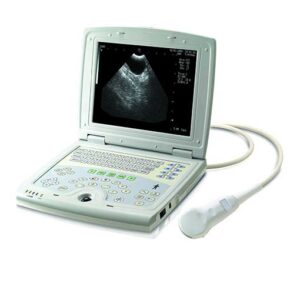

Dcu10 Full Digital Color Doppler Ultrasound Scanner

DCU10 full digital color Doppler ultrasound scanner is available for the diagnosis of abdomen (including GYN and OB), cardiology, vessel and small parts, with the following scanning mode: 2D, CFM, PDI,PW and M to provide the best resolution and sensitivity.

2.1 Dimension: 400 mm(L)´186mm(W)´ 385mm(H), N.W.: 8.8 Kg (without probe)

2.3 Display: 10.4″ high definition & flicker free color medical LCD monitor